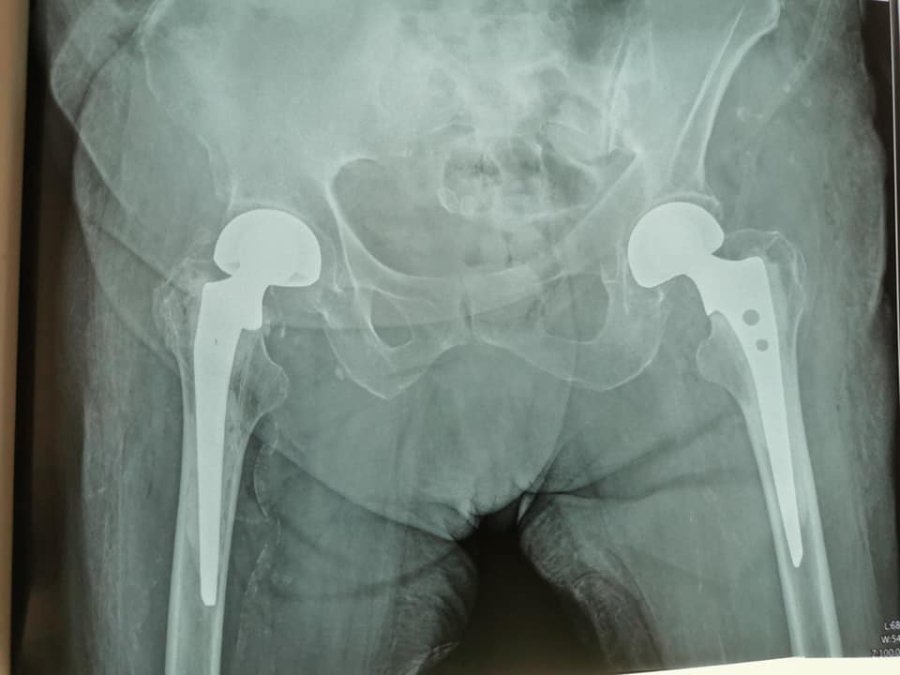

У луцькій лікарні 95-річній жінці замінили суглоби. ФОТО

У Луцькій міській клінічній лікарні у відділенні травматології та ортопедії провели два ендопротезування (заміну суглобів) 95-річній пацієнтці.

8 серпня цього року у відділення поступила пацієнтка, 1926 року народження, з переломом шийки лівої стегнової кістки. Пацієнтці провели біполярне ендопротезування цього стегна.

"Цікаво, що у грудні 2020 року вона поступала до нас з аналогічним переломом шийки правої стегнової кістки, - розповідає завідувач відділення Тарас Куровець, - тоді теж було проведено біполярне ендопротезування. Хвора гарно відновилася після травми. Ходила вже без палочки. І ось знову травма вже іншої ноги. Для старших людей, а тим більше для 95 років, це значна травматизація і єдиний вихід - це ендопротезування", - пишуть у дописі.